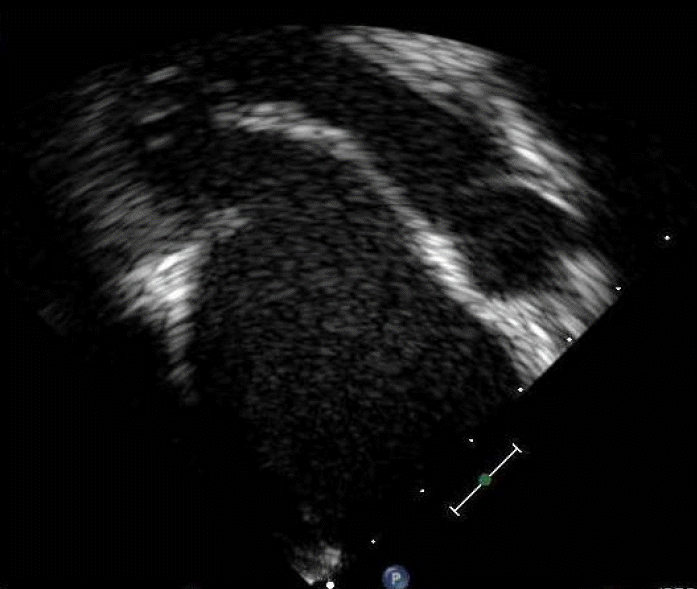

Figure 2.

Transthoracic echocardiography revealed suspicious vegetation (arrow) on the anterior mitral leaflets.